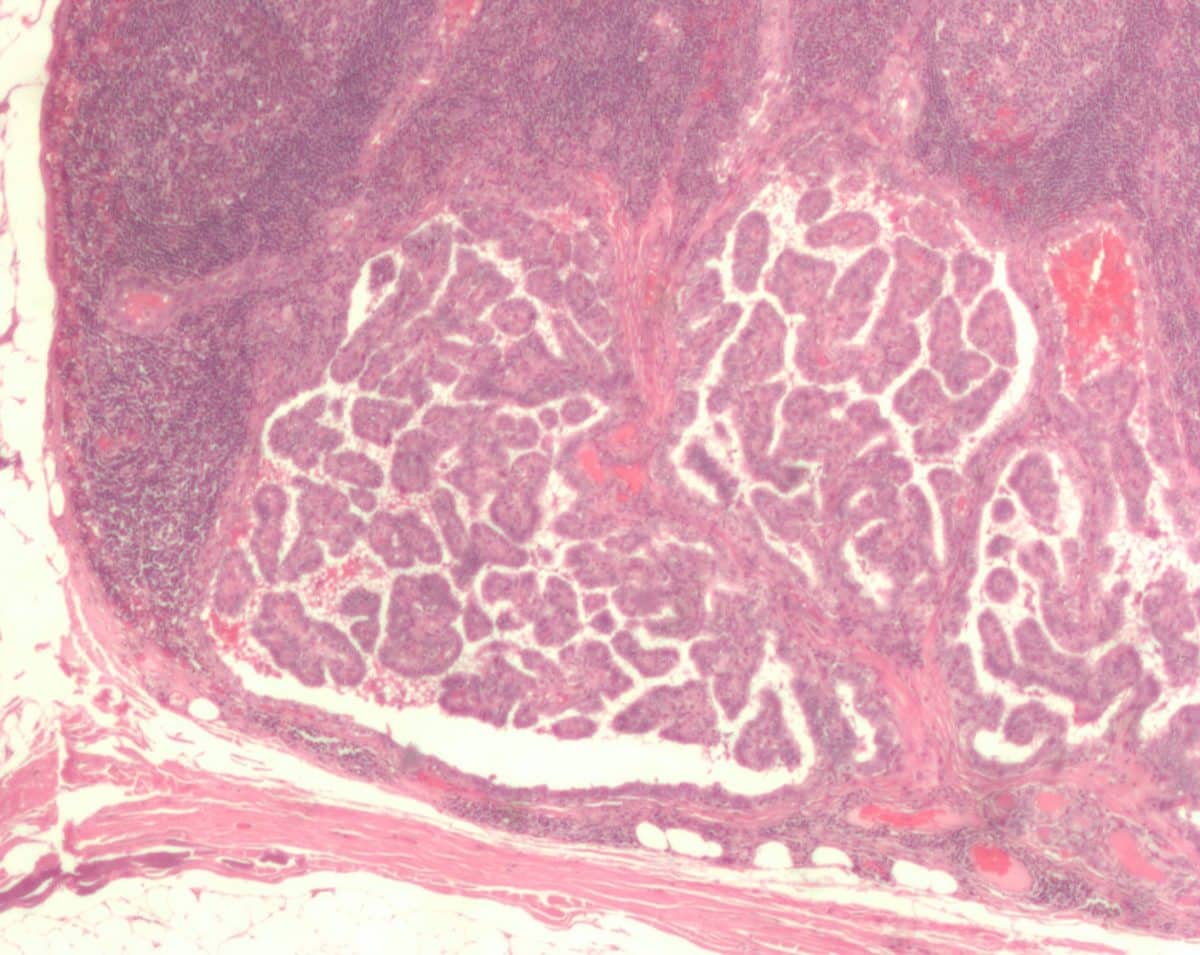

Группа российских ученых разработала прототип установки для лечения рака без проведения тяжелых операций. Опухоль точечно уничтожается микроволновым излучением. Технология подходит, в том числе, для лечения опухолей щитовидной железы и груди.

По словам руководителя проекта Федора Кочетова, за границей существуют такие установки, но в России аналогов пока не было. Комплекс позволяет уничтожать опухоли без проведения полноценных хирургических операций. Энергия микроволн затрагивает область с опухолью, не подвергая здоровые ткани чрезмерному воздействию.

С помощью комплекса можно лечить рак молочной и щитовидной желез, опухоли в легких, почках и печени. Операция с помощью комплекса длится около двадцати минут. При его использовании достаточно местной анестезии.